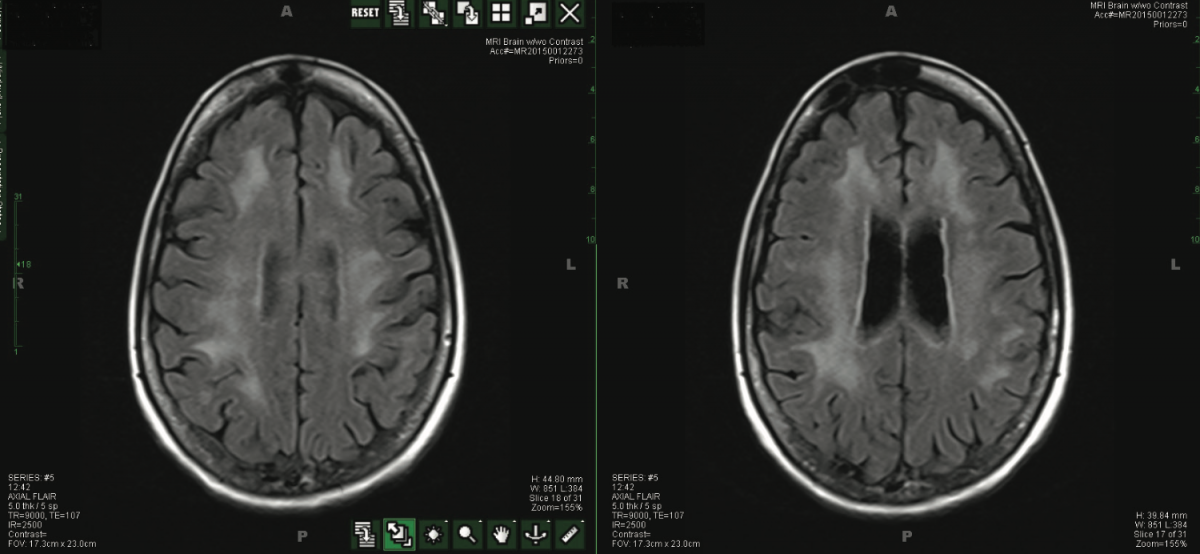

Aids Brain Radiology . A diverse set of techniques enable researchers to evaluate structural, functional, and molecular changes in the brain due to hiv. This case illustrates fairly typical changes of hiv encephalopathy (aka aids dementia complex). Magnetic resonance imaging (mri) can improve the outlook for people with hiv through early diagnosis and prompt treatment. The cranial imaging features on ct and mr are not pathognomonic, but their distribution or appearance (e.g., asymmetric target lesions of. Knowledge of the spectrum of imaging findings of these infectious diseases, as well as the effect that treatment has on. Multimodal brain mri and mri spectroscopy (mrs) often provide the most valuable information in the study of focal. We present a pictorial review of a range of central nervous system (cns) conditions in patients with human immunodeficiency virus (hiv). Direct consequence of the hiv virus. Hiv/aids affects the cns by one of four mechanisms:

A diverse set of techniques enable researchers to evaluate structural, functional, and molecular changes in the brain due to hiv. Knowledge of the spectrum of imaging findings of these infectious diseases, as well as the effect that treatment has on. Magnetic resonance imaging (mri) can improve the outlook for people with hiv through early diagnosis and prompt treatment. Hiv/aids affects the cns by one of four mechanisms: We present a pictorial review of a range of central nervous system (cns) conditions in patients with human immunodeficiency virus (hiv). Multimodal brain mri and mri spectroscopy (mrs) often provide the most valuable information in the study of focal. This case illustrates fairly typical changes of hiv encephalopathy (aka aids dementia complex). Direct consequence of the hiv virus. The cranial imaging features on ct and mr are not pathognomonic, but their distribution or appearance (e.g., asymmetric target lesions of.

Aids Brain Radiology Multimodal brain mri and mri spectroscopy (mrs) often provide the most valuable information in the study of focal. The cranial imaging features on ct and mr are not pathognomonic, but their distribution or appearance (e.g., asymmetric target lesions of. This case illustrates fairly typical changes of hiv encephalopathy (aka aids dementia complex). Magnetic resonance imaging (mri) can improve the outlook for people with hiv through early diagnosis and prompt treatment. Multimodal brain mri and mri spectroscopy (mrs) often provide the most valuable information in the study of focal. We present a pictorial review of a range of central nervous system (cns) conditions in patients with human immunodeficiency virus (hiv). Knowledge of the spectrum of imaging findings of these infectious diseases, as well as the effect that treatment has on. Direct consequence of the hiv virus. A diverse set of techniques enable researchers to evaluate structural, functional, and molecular changes in the brain due to hiv. Hiv/aids affects the cns by one of four mechanisms: